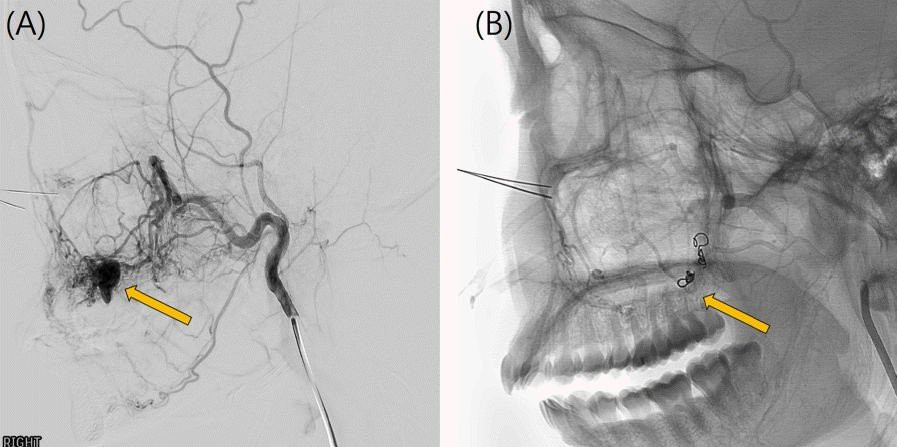

26세 여성이 수개월 전부터 발생한 원인미상의 지속적인 우측 상악 후방부의 잇몸 출혈을 주소로 의뢰되어 구강악안면외과 외래에 내원하였다. 빈혈 이외의 특이 병력은 없었으며, 콘빔 전산화단층촬영(Cone-beam Computed tomography, CBCT)과 파노라마영상을 포함한 단순 진단 영상에서 우측 상악 제2소구치와 제1대구치의 치근단 부위에 직경 12mm의 원형 낭종(Cystic lesion)으로 보이는 병소와 이에 동반된 협측 치조골의 골 침식(Bone erosion)이 관찰되었다(Fig. 1). 병소와 연관되어 있는 치아인 우측 상악 제2소구치와 제1대구치는 전기 치수검사(Electric pulp test)상 생활력이 있었으며, 필요시 술 후에 증상관찰 후 근관 치료를 시행하기로 계획하였다. 방사선 소견 상 반구형의 낭성 종괴, 부드럽고 매끈한 외부경계로 인해 상악동의 점액성 저류낭종(Maxillary mucous retention cyst)일 가능성도 존재했으나 콘빔 전산화단층촬영(CBCT) 상에서 치근부와 연결점이 보인다는 점에서 확률이 낮다고 판단했다[14]. 결국 치근단낭종으로 임시 진단을 내린 후 일주일 뒤 구강악안면외과 외래에서 낭종 적출술을 계획하였다. 빈혈의 기왕력이 있어 일반혈액검사를 실시한 결과, 헤모글로빈 6.7 g/dL, 혈소판 321,000/uL, 프로트롬빈 시간(Prothrombin Time, PT) 13.2 sec, 82.3%, INR 1.11, activated PTT(Partial Thromboplastin Time) 27.9로 외래 수술 시행 전 낮은 헤모글로빈 수치가 관찰되었지만 어지럼증과 같은 임상적 증상은 없었다.구강악안면외과 외래에서 1:100,000 에피네프린이 함유된 2% 리도카인(Lidocaine) 국소마취 하에 낭종 적출술을 시도했으나 수술 중 기구를 치근단 병소 부위로 접근하자마자 대량 출혈(Massive bleeding)이 발생하였으며, 국소적 지혈을 시도하였으나 전혀 지혈이 되지 않았다. 저혈량성 쇼크(Hypovolemic shock) 위험성이 있어 수술을 중단 후 응급실로 이송하였으며, 즉각적으로 적혈구 수혈 및 체액량 보존을 위해 0.9% 생리식염수로 정맥내 수액 공급을 진행하였다. 이어 구내에 발생한 출혈을 조절하기 위해 이어 영상의학과에 의뢰하여 접형구 개동맥(Sphenopalatine artery)과 상악후상치조동맥(Posterior superior alveolar artery)을 대상으로 색전술(Embolization)이 시행되었다(Fig. 2). 응급색전술은 겔폼(Gelfoam), 33% 아교(Glue), 코일(Coil)을 사용하였으며, 성공적으로 출혈을 조절할 수 있었다. 색전술을 시행한 다음날 적절한 혈관 폐색이 이루어졌는지 확인을 위해 전산화 단층 혈관 조영술(Computed tomographic angiography) 촬영을 진행하였다. 접형구개동맥이 폐색되어 있음을 확인하였고, 공급혈관(Feeding vessel) 내에 코일이 적절히 위치해 있었으며, 후상치조동맥에서 기원한 분지 내에서 병변 주변으로 이루어진 glue casting이 관찰되었다(Fig. 3). 이러한 영상 판독 결과를 통해 병변의 혈관 공급이 성공적으로 차단되었음을 확인하였다. 골내 혈관종의 다양한 방사선소견으로 인해 초기에 치근단낭종으로 오인되었음을 확인하였고, 이에 따라 낭종적출술이 아닌 골내혈관종의 수술적 절제를 계획하였다.색전술을 시행한지 이틀 째에 국소마취 하 혈관종의 절제술이 이루어졌다. 협측으로 접근하여 15번 외과용 칼(No.15 Surgical blade)와 골막기자(Periosteal elevator)로 조심스럽게 골막점막피판을 거상한 후에 종양을 주변 조직으로부터 박리하여 모스키토 지혈겸자(Mosquito forcep)로 종양을 제거하였다. 이 과정에서 치근단이 병변과 긴밀하게 연접하고 있는 상악 우측 제2소구치의 경우, 협측 골이 상당히 소실되어 있는 상태로 3도의 동요도를 보여 결국 발치를 하기로 결정하였다. 골 결손 부위와 발치와는 추후 임플란트 식립을 고려해 이종골 이식재와 흡수성 차폐막을 적용해 골이식을 시행하였다.수술적 제거 이후 2개월 추적관찰에서 재발 또는 잔여 증상은 관찰되지 않았다. 임상검사 및 방사선 영상검사에서 골 치유가 만족스럽게 이루어졌으며, 우측 상악 제1대구치에서 동요 또는 타진 통증 없이 환자는 무증상 상태를 유지하였다(Fig. 4). 수술 3개월 후 환자는 안정적인 골 치유와 충분한 각화 치은이 생성된 것을 확인되어 우측 상악 제2소구치부위의 고정체 식립을 위한 임플란트 1차 수술을 시행하였다. 이어 3개월 뒤 임플란트 치유지대주를 연결하는 임플란트 2차 수술 및 상부 보철물 수복을 완료하였으며, 경과 관찰 시 수술부위의 별다른 증상이나 재발의 증거는 없었고, 합병증은 발생하지 않았다.

Figure 4.

Postoperative imaging taken two months after mass resection, and socket preservation using GBR(Guided Bone Regeneration) following the extraction of right maxillary second premolar. (A) Panoramic X-ray shows successful integration of the bone graft at the surgical site. (B) Sagittal view and (C) coronal view of Cone Beam Computed Tomography (CBCT) demonstrate the volumetric bone healing in the right maxillary posterior region.